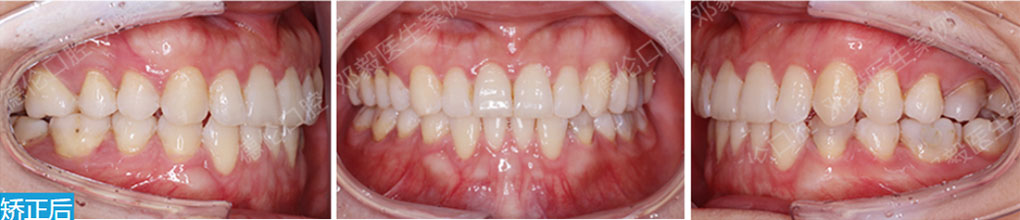

矯治采用兩種不同的厚度的膜片(牙套),發揮兩種不同膜片的各自優勢,在有效的作用時間內,矯治效率、矯治目標達成和舒適度方面較普通隱形矯正方式有明顯提升。

厚薄兩種矯治器,每周替換有利于牙齒位置的準確控制